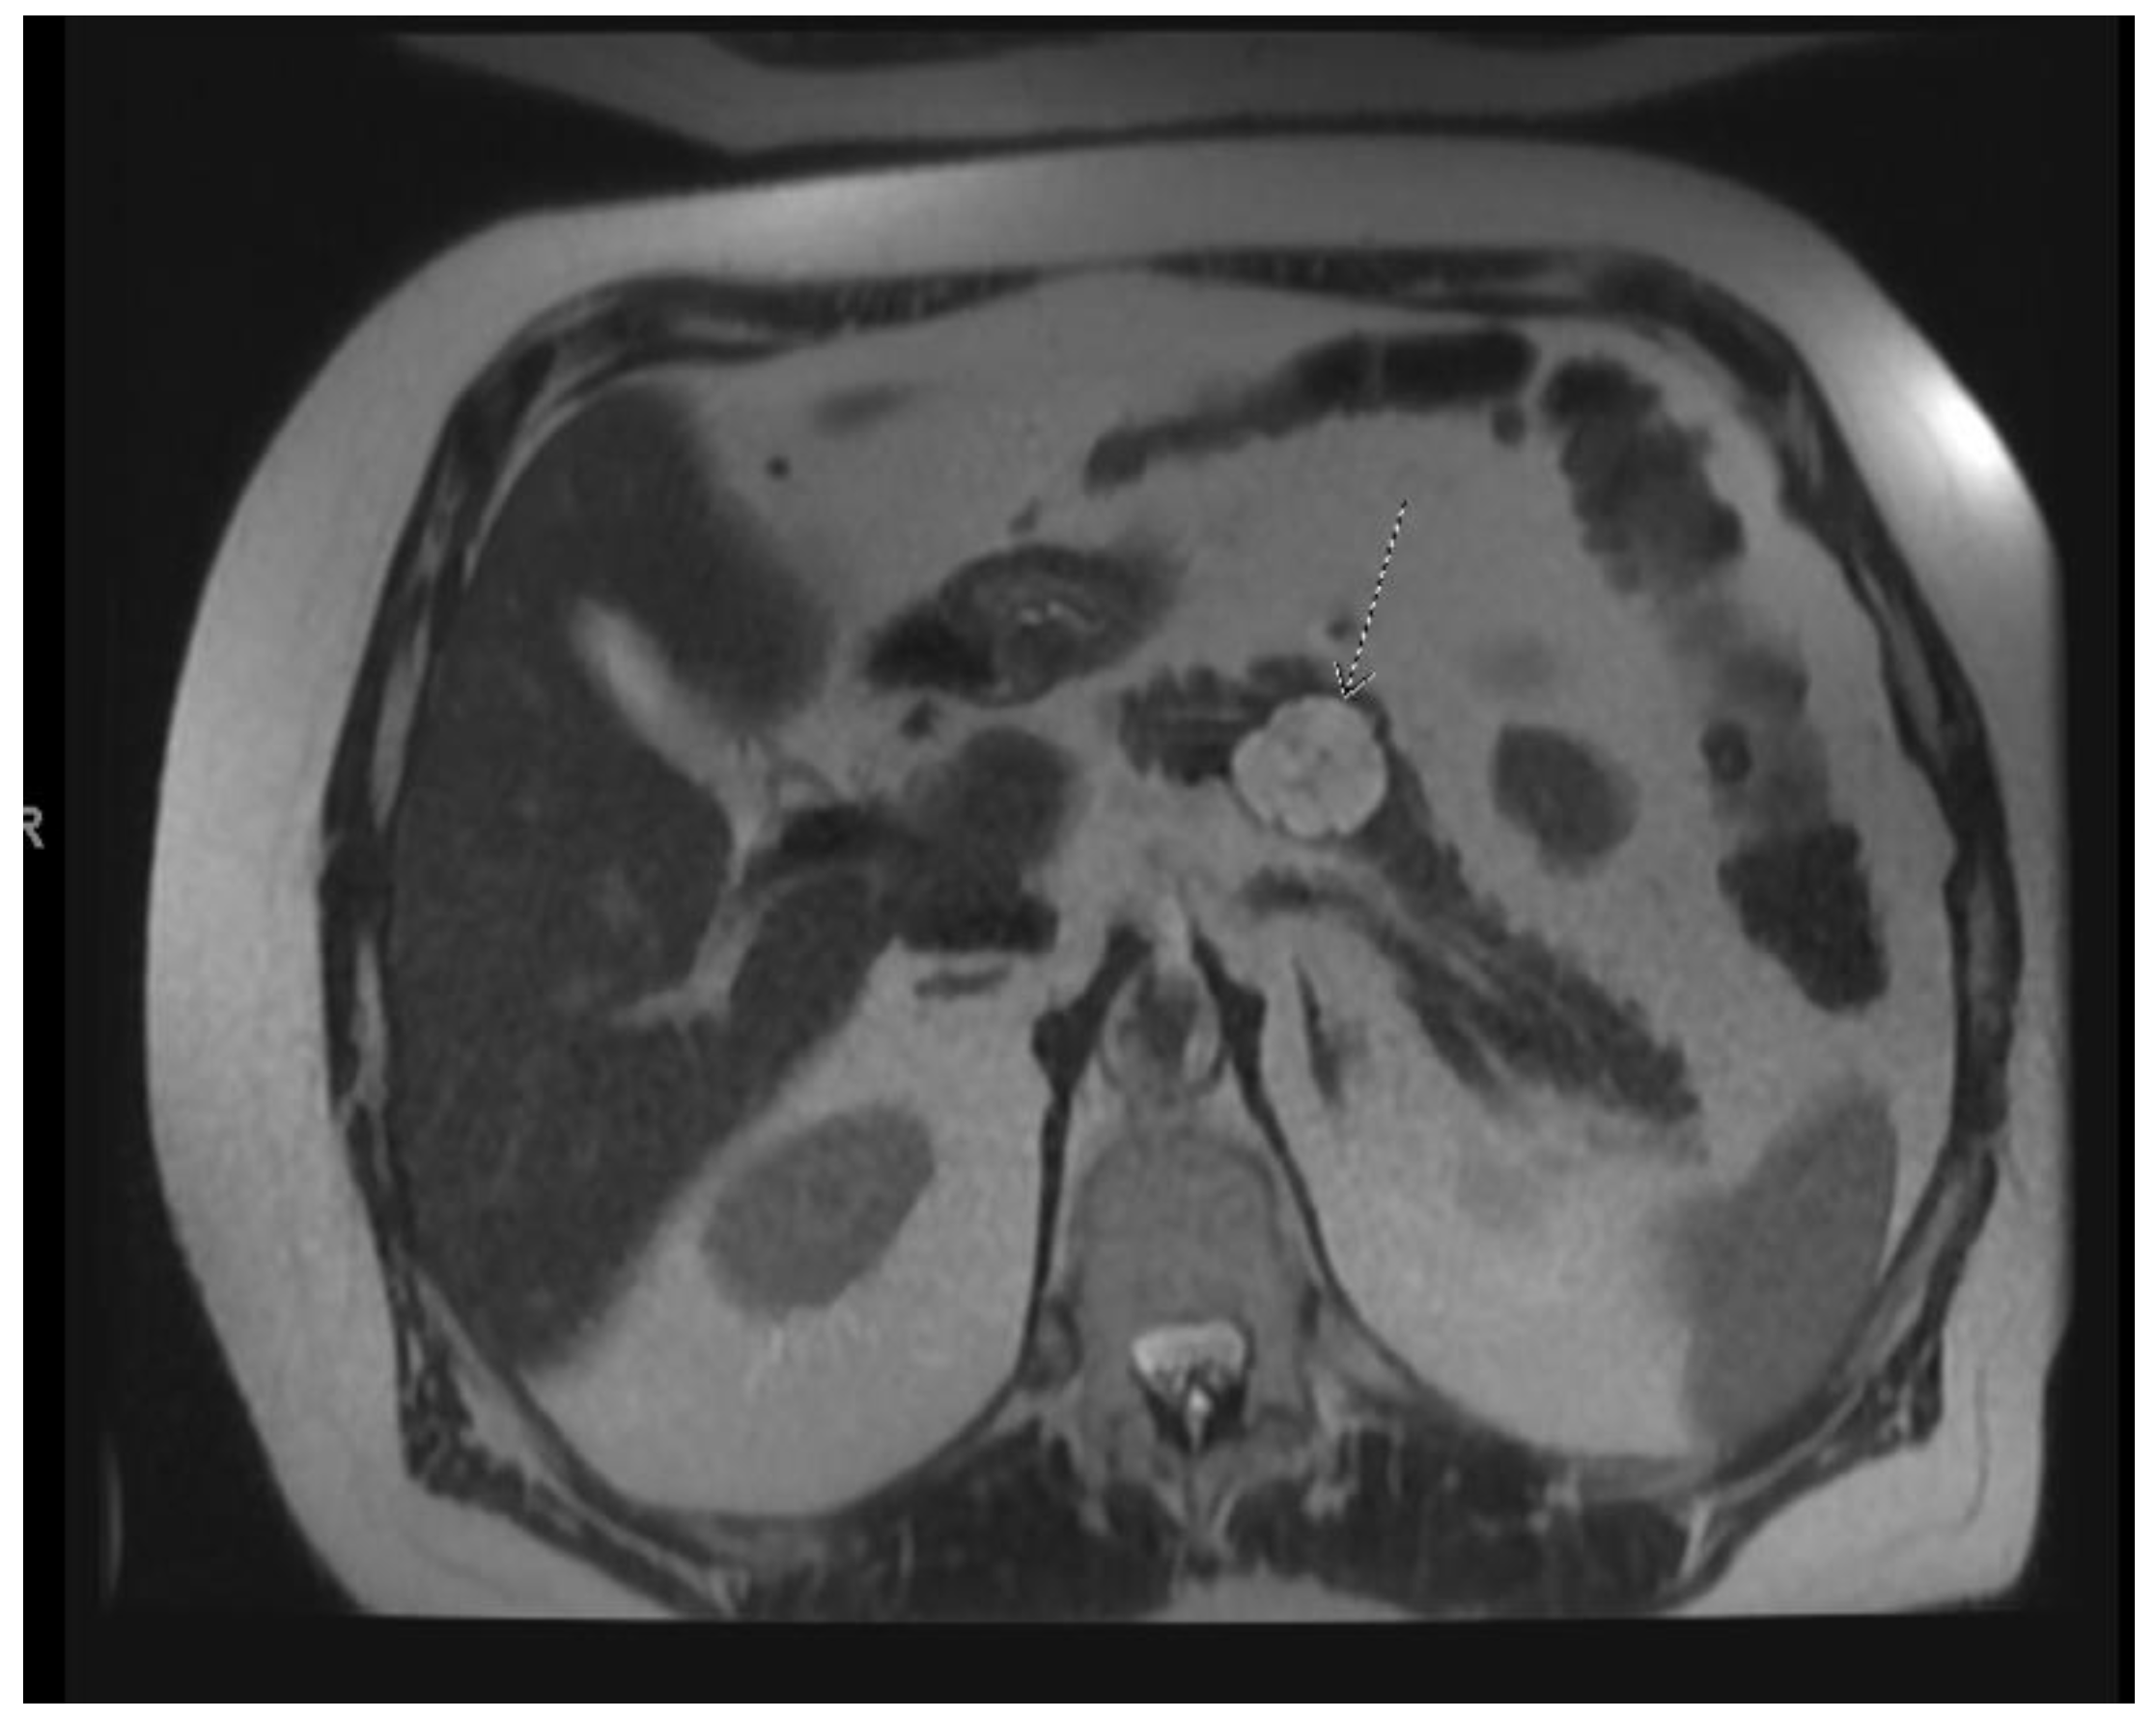

Figure 4.

MRI image of mixed IPMN.

IPMNs can be divided into main duct intraductal papillary mucinous neoplasm and branch duct intraductal papillary mucinous neoplasms, with dilation of the main pancreatic duct helping to distinguish between the two. They usually present in the fifth to seventh decade of life and have an equal distribution between males and females [15]. Intraductal neoplasms are typically associated with a dilated main pancreatic duct (Figure 2a,b), whereas the branch duct IPMNs are associated with a dilated pancreatic duct branch or branches (Figure 3). A mixed IPMN is defined as a cystic lesion with ductal communication and main pancreatic duct dilation greater than or equal to 5 mm (Figure 4). Diabetes mellitus (DM) and a family history of pancreatic adenocarcinoma are known risk factors for IPMN, with odds ratios of 1.79 (CI 95%: 1.08–2.98) and 2.94 (CI 95%: 1.17–7.39), respectively [16]. Cytology can show columnar cells with variable atypia and can stain positive for mucin. CEA is usually greater than 200 ng/mL in approximately 75% of lesions, similar to mucinous neoplasms. Main duct IPMNs have a 36–100% risk of malignant potential, compared to a lower risk of 11–30% malignant potential of side branch IPMNs [17].